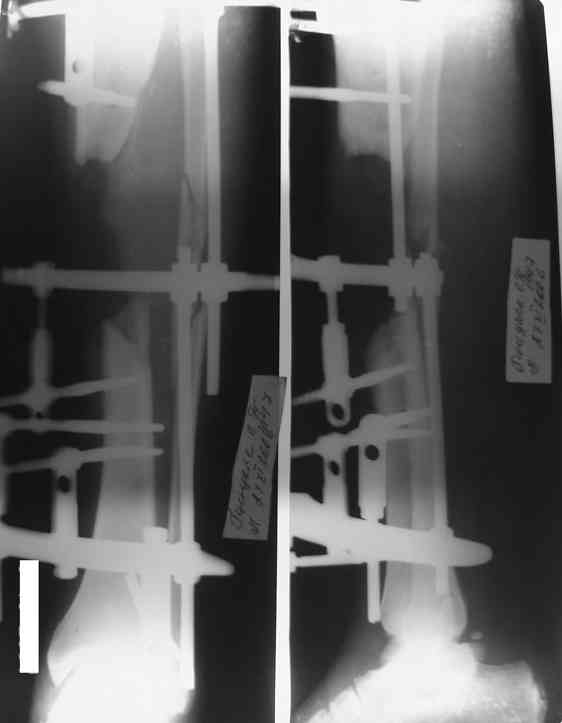

[Ortho] Дефект и остеомиелит tibia

Хотелось бы уточнить позицию по д-зу на данный момент-Хронических заболеваний у пациента нет.  Свищ по передней поверхности в проксимальном отделе дистального фрагмента до 3 мм. Выделения серозно- геморагического характера. Явных признаков воспааления м/т нет и не было на протяжении 4 мес.

Доводим также к сведенью что дистальный межберцевый синастоз уже состоялся, ложный сустав малоберцевой кости в с/з. Учитывая так же отсутстаие нормального обеспечения больного в послеоперационном периоде мы склоняемся к аппарату внешней фиксации.

Как дополнение высылаю снимки и фото конечности, чтобы Вы могли оценить состояние м/т, и течение заболевания.